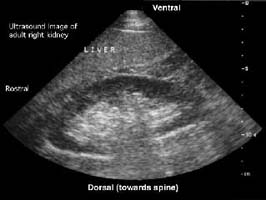

»ç±¸Ã¼ ÁúȯµéÀÇ

Áø´ÜÀº ¼Òº¯ ¹× Ç÷¾× »ýÈÇÐ °Ë»ç, Ç÷û

°Ë»ç, ½Å»ý°Ë µîÀ¸·Î ³»·ÁÁý´Ï´Ù. ¼Òº¯°Ë»ç»ó

Ç÷´¢¿Í ´Ü¹é´¢ À¯¹«¸¦ ¾Ë¾Æº¸°í, Ç÷¾×

»ýÈÇÐ °Ë»ç»ó ½Å±â´É ÁöÇ¥ÀÎ Å©·¹¾ÆÆ¼´Ñ°ú

Ç÷Áß ¿ä¼Ò Áú¼Ò, ±×¹Û¿¡ ÄÝ·¹½ºÅ×·Ñ, ¾ËºÎ¹Î

µîÀÇ ¼öÄ¡¸¦ Á¶»çÇÕ´Ï´Ù. Ç÷û °Ë»ç»ó

»ç±¸Ã¼½Å¿°ÀÇ °¡´ÉÇÑ ¿øÀÎÀÎ BÇü °£¿°°ú

CÇü °£¿° Ç¥½ÄÀÚ, È«¹Ý¼º ³¶Ã¢ÀÇ Ç×ÇÙÇ×ü,

Ç÷û º¸Ã¼ÀÇ °¨¼Ò µîÀ» Á¶»çÇÕ´Ï´Ù. ¸¶Áö¸·À¸·Î

½Å»ý°ËÀ¸·Î Á¤È®ÇÑ Áø´Ü¸íÀ» ¾òÀ¸¸é ±×

ÁúȯÀÇ ¿¹Èĸ¦ ÃßÁ¤ÇÒ ¼ö ÀÖÀ¸¸ç Ä¡·á¹ýÀÌ

Á¤ÇØÁý´Ï´Ù. ½Å»ý°ËÀº ½ÅÀåÀü¹®Àǰ¡ ½ÃÇàÇϹǷÎ

°ÅÀÇ ¾ÈÀüÇÏ¸ç ½ÅÀå¿¡´Â Ç÷°üÀÌ ¸¹À¸¹Ç·Î

ÀϺο¡¼ ÃâÇ÷ÇÒ ¼ö ÀÖÀ¸³ª Á¶Á÷°Ë»çÈÄ

¸ð·¡ÁÖ¸Ó´Ï·Î ¾Ð¹Ú ÁöÇ÷ÇÏ°í ¾ÈÁ¤À» ÃëÇϸé

Å« À§ÇèÀº °ÅÀÇ ¾ø½À´Ï´Ù.